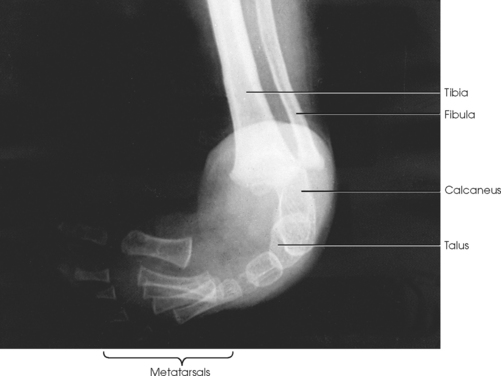

The foot consists of 26 bones (Figs. 6-1 and 6-2):

Fig. 6-2 Right foot. A, Medial aspect. B, Lateral aspect. C, Coronal section near base of metatarsals. Transverse arch shown.

The bones of the foot are similar to the bones of the hand. Structural differences permit walking and support of the body’s weight. For descriptive purposes, the foot is sometimes divided into the forefoot, midfoot, and hindfoot. The forefoot includes the metatarsals and toes. The midfoot includes five tarsals—the cuneiforms, navicular, and cuboid bones. The hindfoot includes the talus and calcaneus. The bones of the foot are shaped and joined together to form a series of longitudinal and transverse arches. The longitudinal arch functions as a shock absorber to distribute the weight of the body in all directions, which permits smooth walking (see Fig. 6-2). The transverse arch runs from side to side and assists in supporting the longitudinal arch. The superior surface of the foot is termed the dorsum or dorsal surface, and the inferior, or posterior, aspect of the foot is termed the plantar surface.

The proximal foot contains seven tarsals (see Fig. 6-1):

The talus, irregular in form and occupying the superiormost position of the foot, is the second largest tarsal bone (see Figs. 6-1 to 6-3). The talus articulates with four bones—tibia, fibula, calcaneus, and navicular bone. The superior surface, the trochlear surface, articulates with the tibia and connects the foot to the leg. The head of the talus is directed anteriorly and has articular surfaces that join the navicular bone and calcaneus. On the inferior surface is a groove, the sulcus tali, that forms the roof of the sinus tarsi. The inferior surface also contains three facets that align with the facets on the superior surface of the calcaneus.